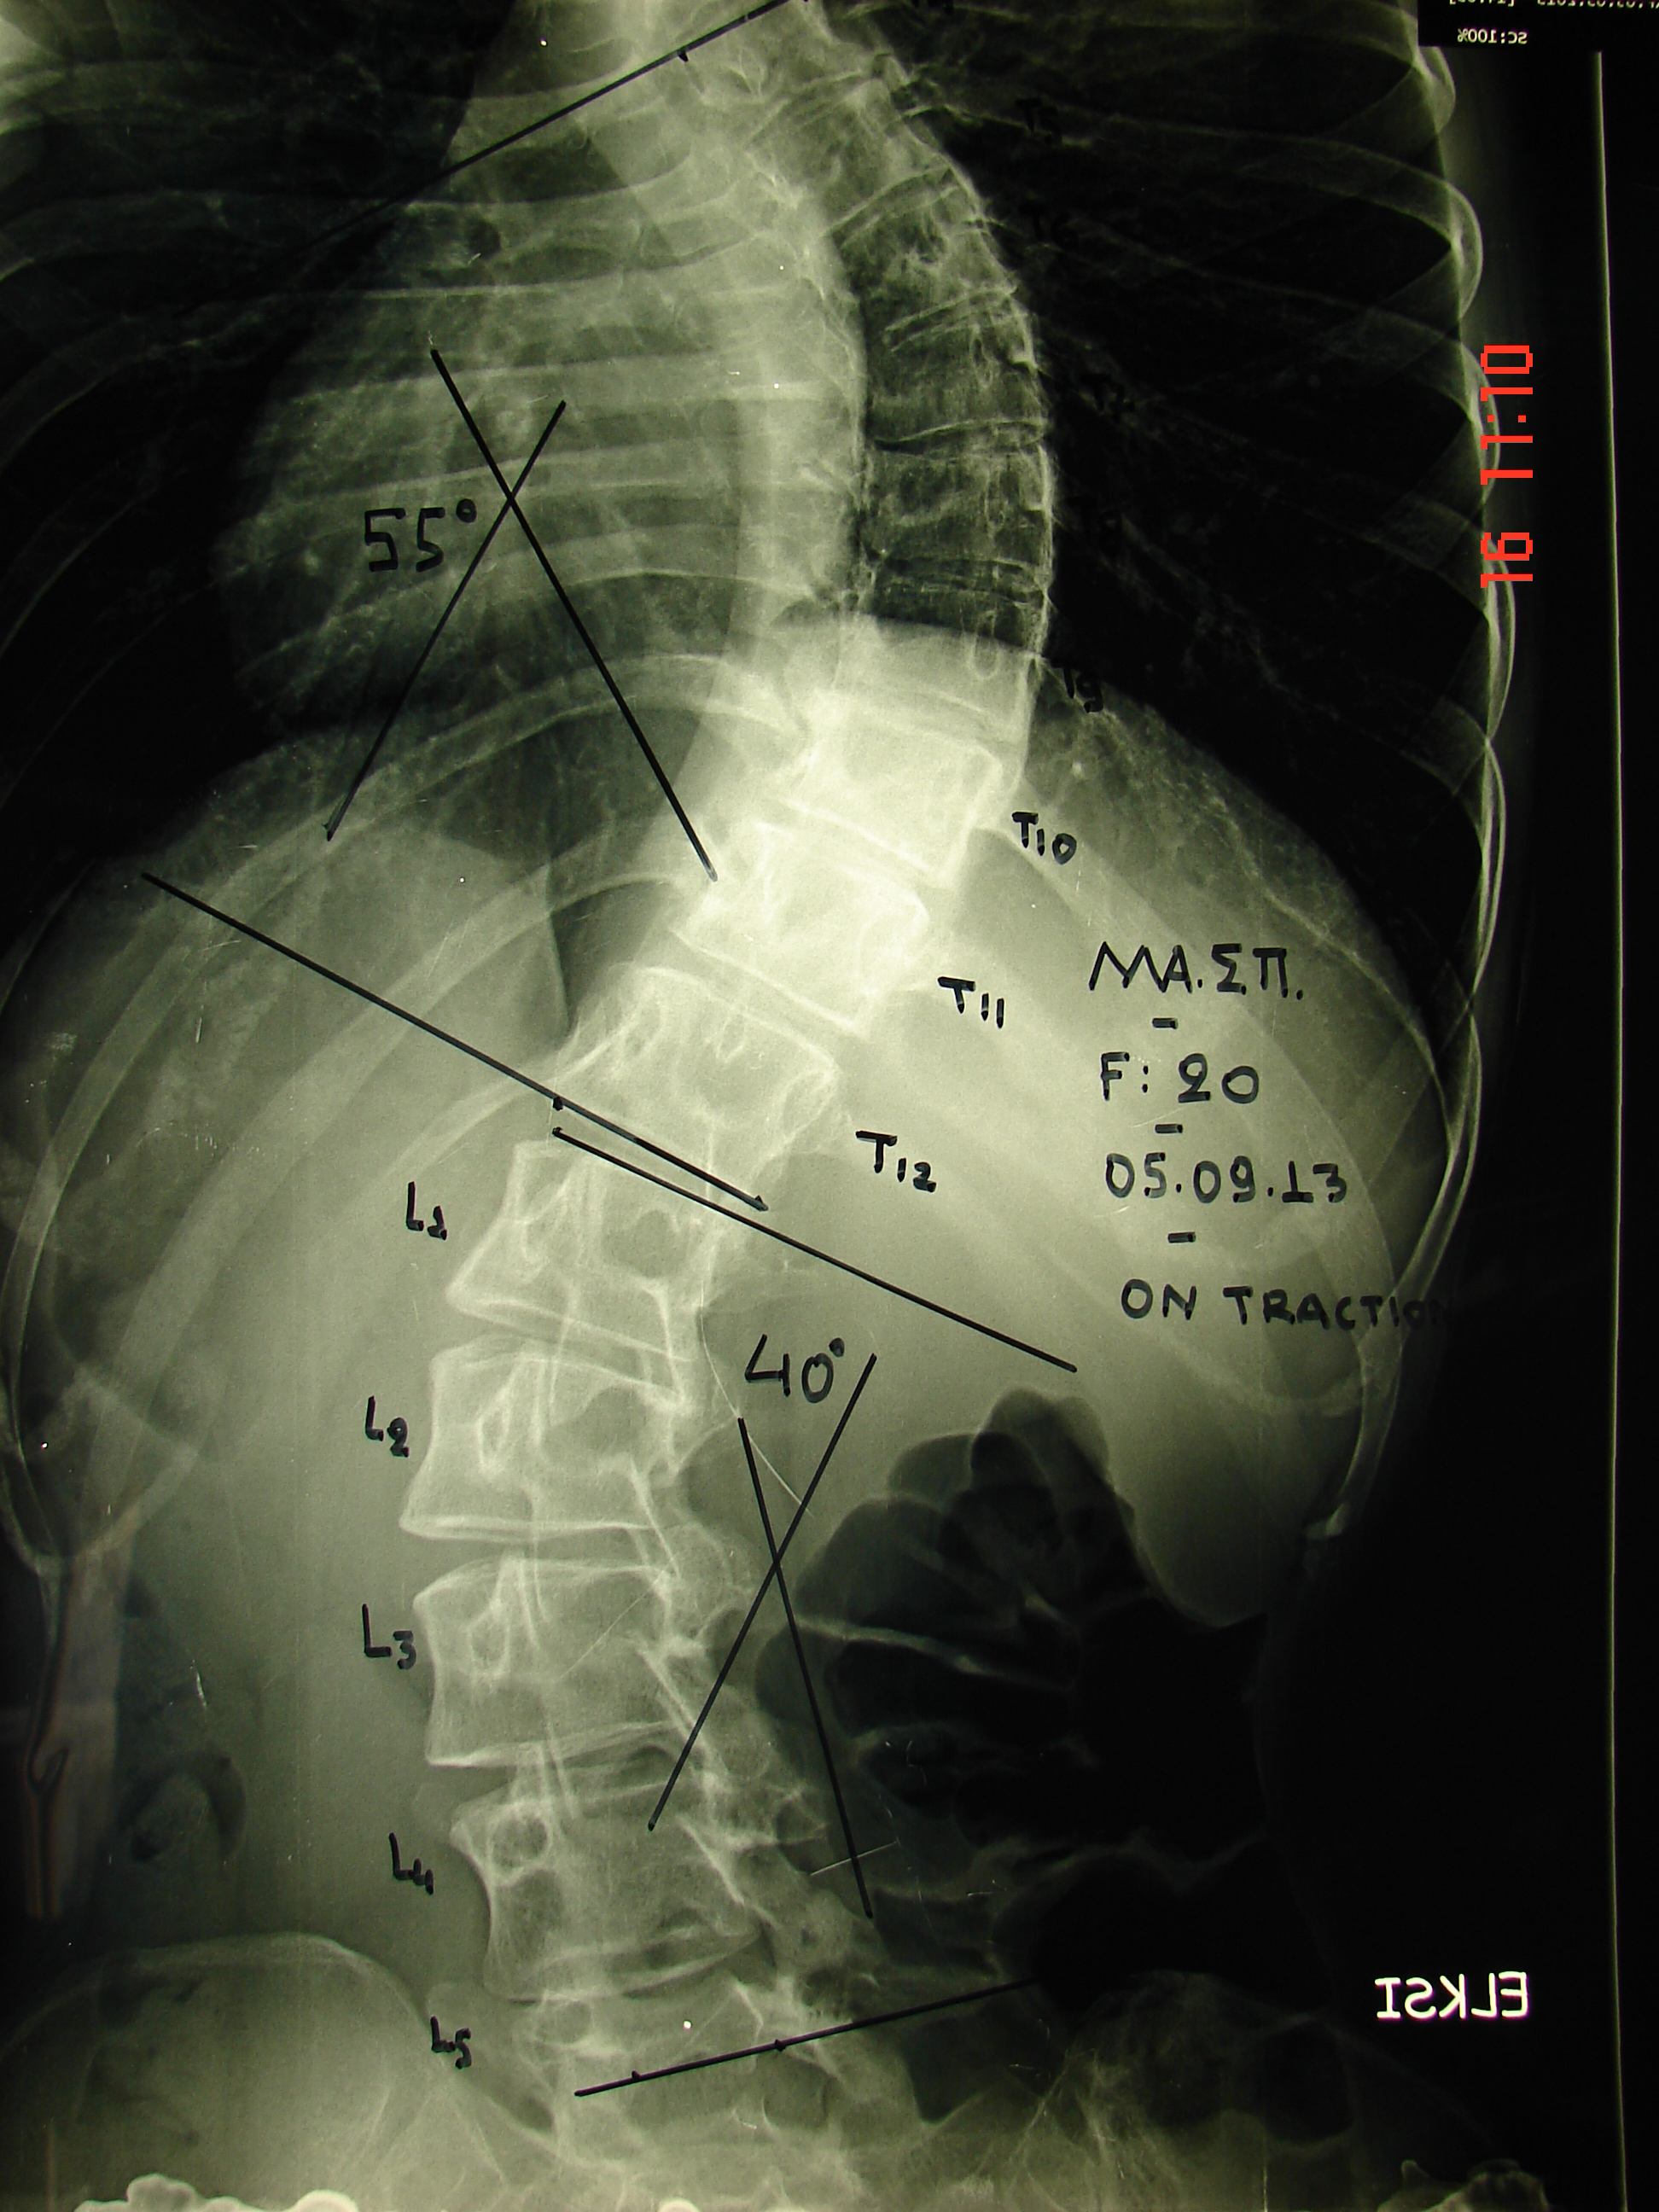

Εικόνα 2α

Ακτινογραφία Σ.Σ. με μέγιστη έλξη της Σ.Σ.

Τα σκολιωτικά κυρτώματα κατέρχονται στις 55 και 40 μοίρες αντίστοιχα